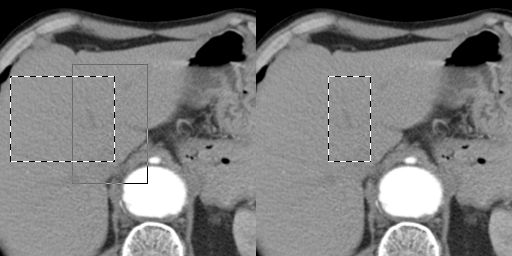

Selection Addition

Before you select the second area hold down the <Shift> key of the keyboard, and then use your mouse for the second selection.

Selection Subtraction

Before you select the second area hold down the <Ctrl> key of the keyboard, and then use your mouse for the second selection.

Selection Intersection (common area)

Before you select the second area hold down the <Shift> and <Ctrl> keys of the keyboard, and then use your mouse for the second selection.

In the examples is used the selection rectangle tool.